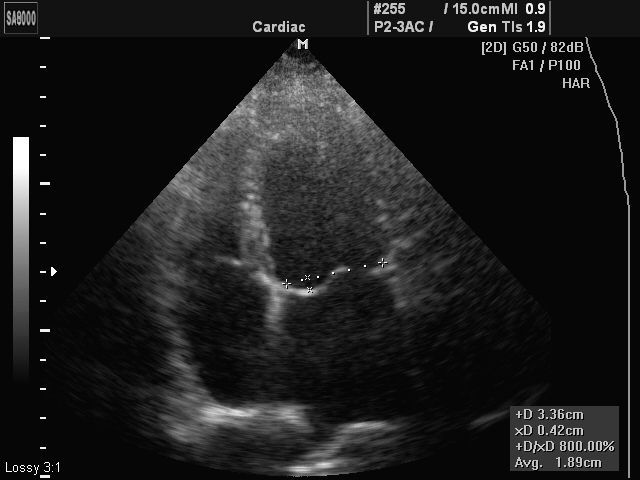

Диагностика трепетания предсердий осуществляется кардиологом. Первым шагом к установлению диагноза является электрокардиография, которая фиксирует аномалии в сердечном ритме. В дополнение к этому применяются следующие методы обследования:

- Ультразвуковое исследование сердечных клапанов, влияющих на аритмию, помогает выявить даже незначительные изменения в размерах сердечных камер и сокращениях миокарда.